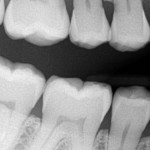

Anyhow, have you ever thought about what your teeth look like?

What I’m asking is, have you ever thought about what your teeth would look like if your face were missing and you could see them without your face getting in the way? Well, I found out and I’m going to share my teeth with you right now.

Without further ado, here is what my teeth would look like if you could only see in black and white and I had no face and you could also see into my actual teeth:

Each thumbnail image is clickable/tappable and when clicked/tapped will take you to a larger image! Of my teeth without my face in the way!

This was before the cleaning, so pardon the two years of calculus! Plus there’s something weird about the lighting! They look cleaner now!